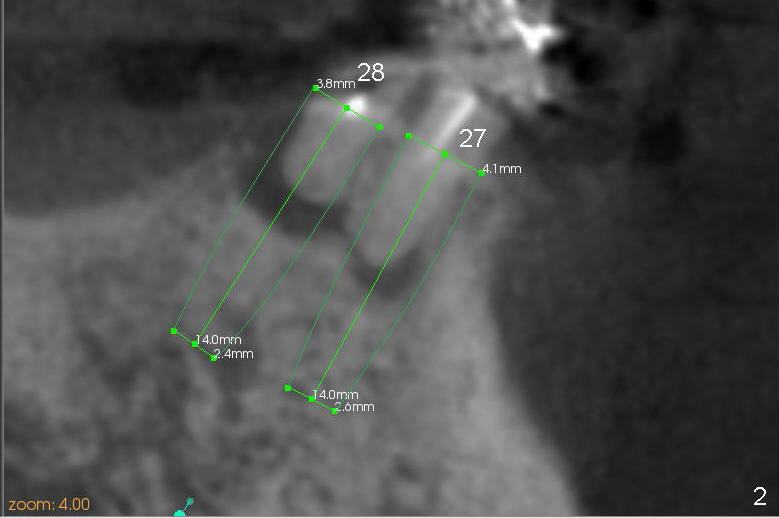

A 85-year-old man has poor dentition (Fig.9). Multiple implants are to be placed at one or two stages (#26-30). If primary stability is obtained for individual implants, they are splinted and immediate provisional is fabricated.

Fig.1-3 are CBCT sagittal sections of the lower right quadrant, whereas Fig.4-8 are coronal sections. The lower left quadrant has been restored.

The sockets of #27,28 will be treated with 2% Xylocaine/1.:50,000 Epinephrine as control group of the antibiotic study.